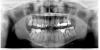

lano Опубликовано 13 августа, 2011 Автор Поделиться Опубликовано 13 августа, 2011 (изменено) Kirovsasa, спасибо за быстрый ответ!Вот мой снимок: Как найти клинику, в которой есть необходимое оборудование, и, специалисты, конечно? Интересует Рига или Санкт-Петербург. Изменено 13 августа, 2011 пользователем lano Ссылка на комментарий

Skip Опубликовано 14 августа, 2011 Поделиться Опубликовано 14 августа, 2011 Спасибо Skip! Очень карасивая картинка . Здесь на ТРГ - вся "система" - череп-сустав-шея. А для чего именно она необходима? Это, всего лишь, часть того комплексного обследования, о котором здесь уже говорили и не даёт никакой информации, в отношении именно внутрисуставной патологии. На боковой ТРГ мы проводим анализ тех скелетных нарушений, коррекция которых может быть включена в общий план реабилитации. Дело в том, что существует определённый мировой стандарт в последовательности проводимых методов диагностики пациентов, страдающих дисфункцией ВНЧС, где каждый из этих методов несёт свою информацию. Мне, например, было уже видно на панорамном снимке проблему в области левого сустава, но только лишь по ОПТГ диагноз поставить невозможно. МРТ даёт хорошую визуализацию внутрисуставных элементов, но я прибегаю к этому методу лишь в каких-то исключительных случаях и отдаю предпочтение сонографии суставов и компьютерному исследованию движений нижней челюсти. На консультации у ортодонта мне говорили, что нужно будет обязательно показаться остеопату - т.к. "неполадки" с суставом могут повлечь за собой проблемы в шейном отделе позвоночника. Это не так, причины проблем с шейным отделом позвоночника приходят из другой области.У меня они уже есть - шейная миалгия и сильные головные боли, кроме этого небольшое ухудшение слуха и шум в левом ухе (проблемный сустав-левый). Может ли все это быть результатом травмы сустава? Насколько реально избавиться от этого после восстановления сустава?Спасибо за ответ!Можете и к остеопату показаться, но толку мало будет без стоматолога, а вернее без такой тесной кооперации - стоматолог+остеопат. Существует определённые виды деформации черепа, при котором в 100% будут, как дисфункция ВНЧС, так и головные боли, включая и шейный отдел позвоночника. В отношении проблем со слухом, как собственно и с суставами, причины лежат всё там же, т.е. должны существовать определённые условия для развития этих нарушений - и это всё в нашем черепе.Вот один из вариантов такой деформации, обычно результат родовой травмы, но может и в раннем детстве случиться: http://s61.radikal.ru/i173/1108/6d/dcba32a1799e.jpg Все эти проблемы решаются... Ссылка на комментарий